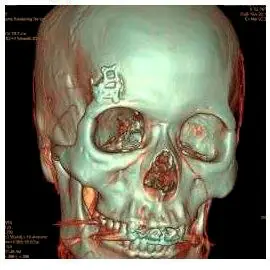

Перед операцией проведут компьютерную нейронавигацию: по КТ и МРТ хирург спланирует каждое действие с точностью до миллиметра. После чего опухоль удалят методом keyhole surgery («хирургия замочной скважины»).

Мне показали, что над бровью просверлят отверстие и через него удалят каверному. Голову не будут брить налысо, только немного подстригут волосы в том месте, где будет место разреза.

Классическая краниотомия (трепанация черепа) — после такой операции сильно повреждаются череп, нужно брить голову, восстанавливаться от месяца до полугода

Плюс хирургии замочной скважины в том, что минимально травмируется череп, не нужно полностью брить голову и восстанавливаться после лечения занимает неделю

Доктор сказал, что во время операции возьмут биопсию. Это метод диагностики, при котором из организма забирают больные ткани и клетки для изучения. С его помощью можно подтвердить онкологическое заболевание.

Через два дня после консультации меня записали на операцию. Она проходила под полным наркозом и заняла 3,5 часа. Хотя по плану она должна была занять всего около полутора часов.

«Экспресс-биопсия показала предположительно злокачественные клетки. Поэтому время операции увеличилось. Из-за подозрения на онкологию мне сделали широкое иссечение — как делают при злокачественных опухолях.»

Доброкачественную опухоль удаляют прямо по контуру, максимально сохраняя соседние ткани. Но для удаления злокачественных образований используют широкое иссечение с захватом здоровых тканей. В моем случае это было необходимо, потому что врач заподозрил развитие рака — и не ошибся. Послеоперационное исследование подтвердило его догадку.